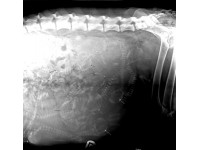

THE PITFALLS OF WORKING WITHIN THE FIELD OF VETERINARY ULTRASOUND – FACTORS PRACTITIONERS SHOULD CONSIDER

For those specialised within the veterinary field, the limitations of working with animal species are all too clear. Human research has adopted the role of the ‘benchmark’ by which veterinary research is compared, despite the importance of the latter in its own right. Nevertheless, ultrasound imaging has been carried out on a number of animal species, including those that could be considered more ‘unconventional’: ranging from snakes, to hyenas and even elephants.